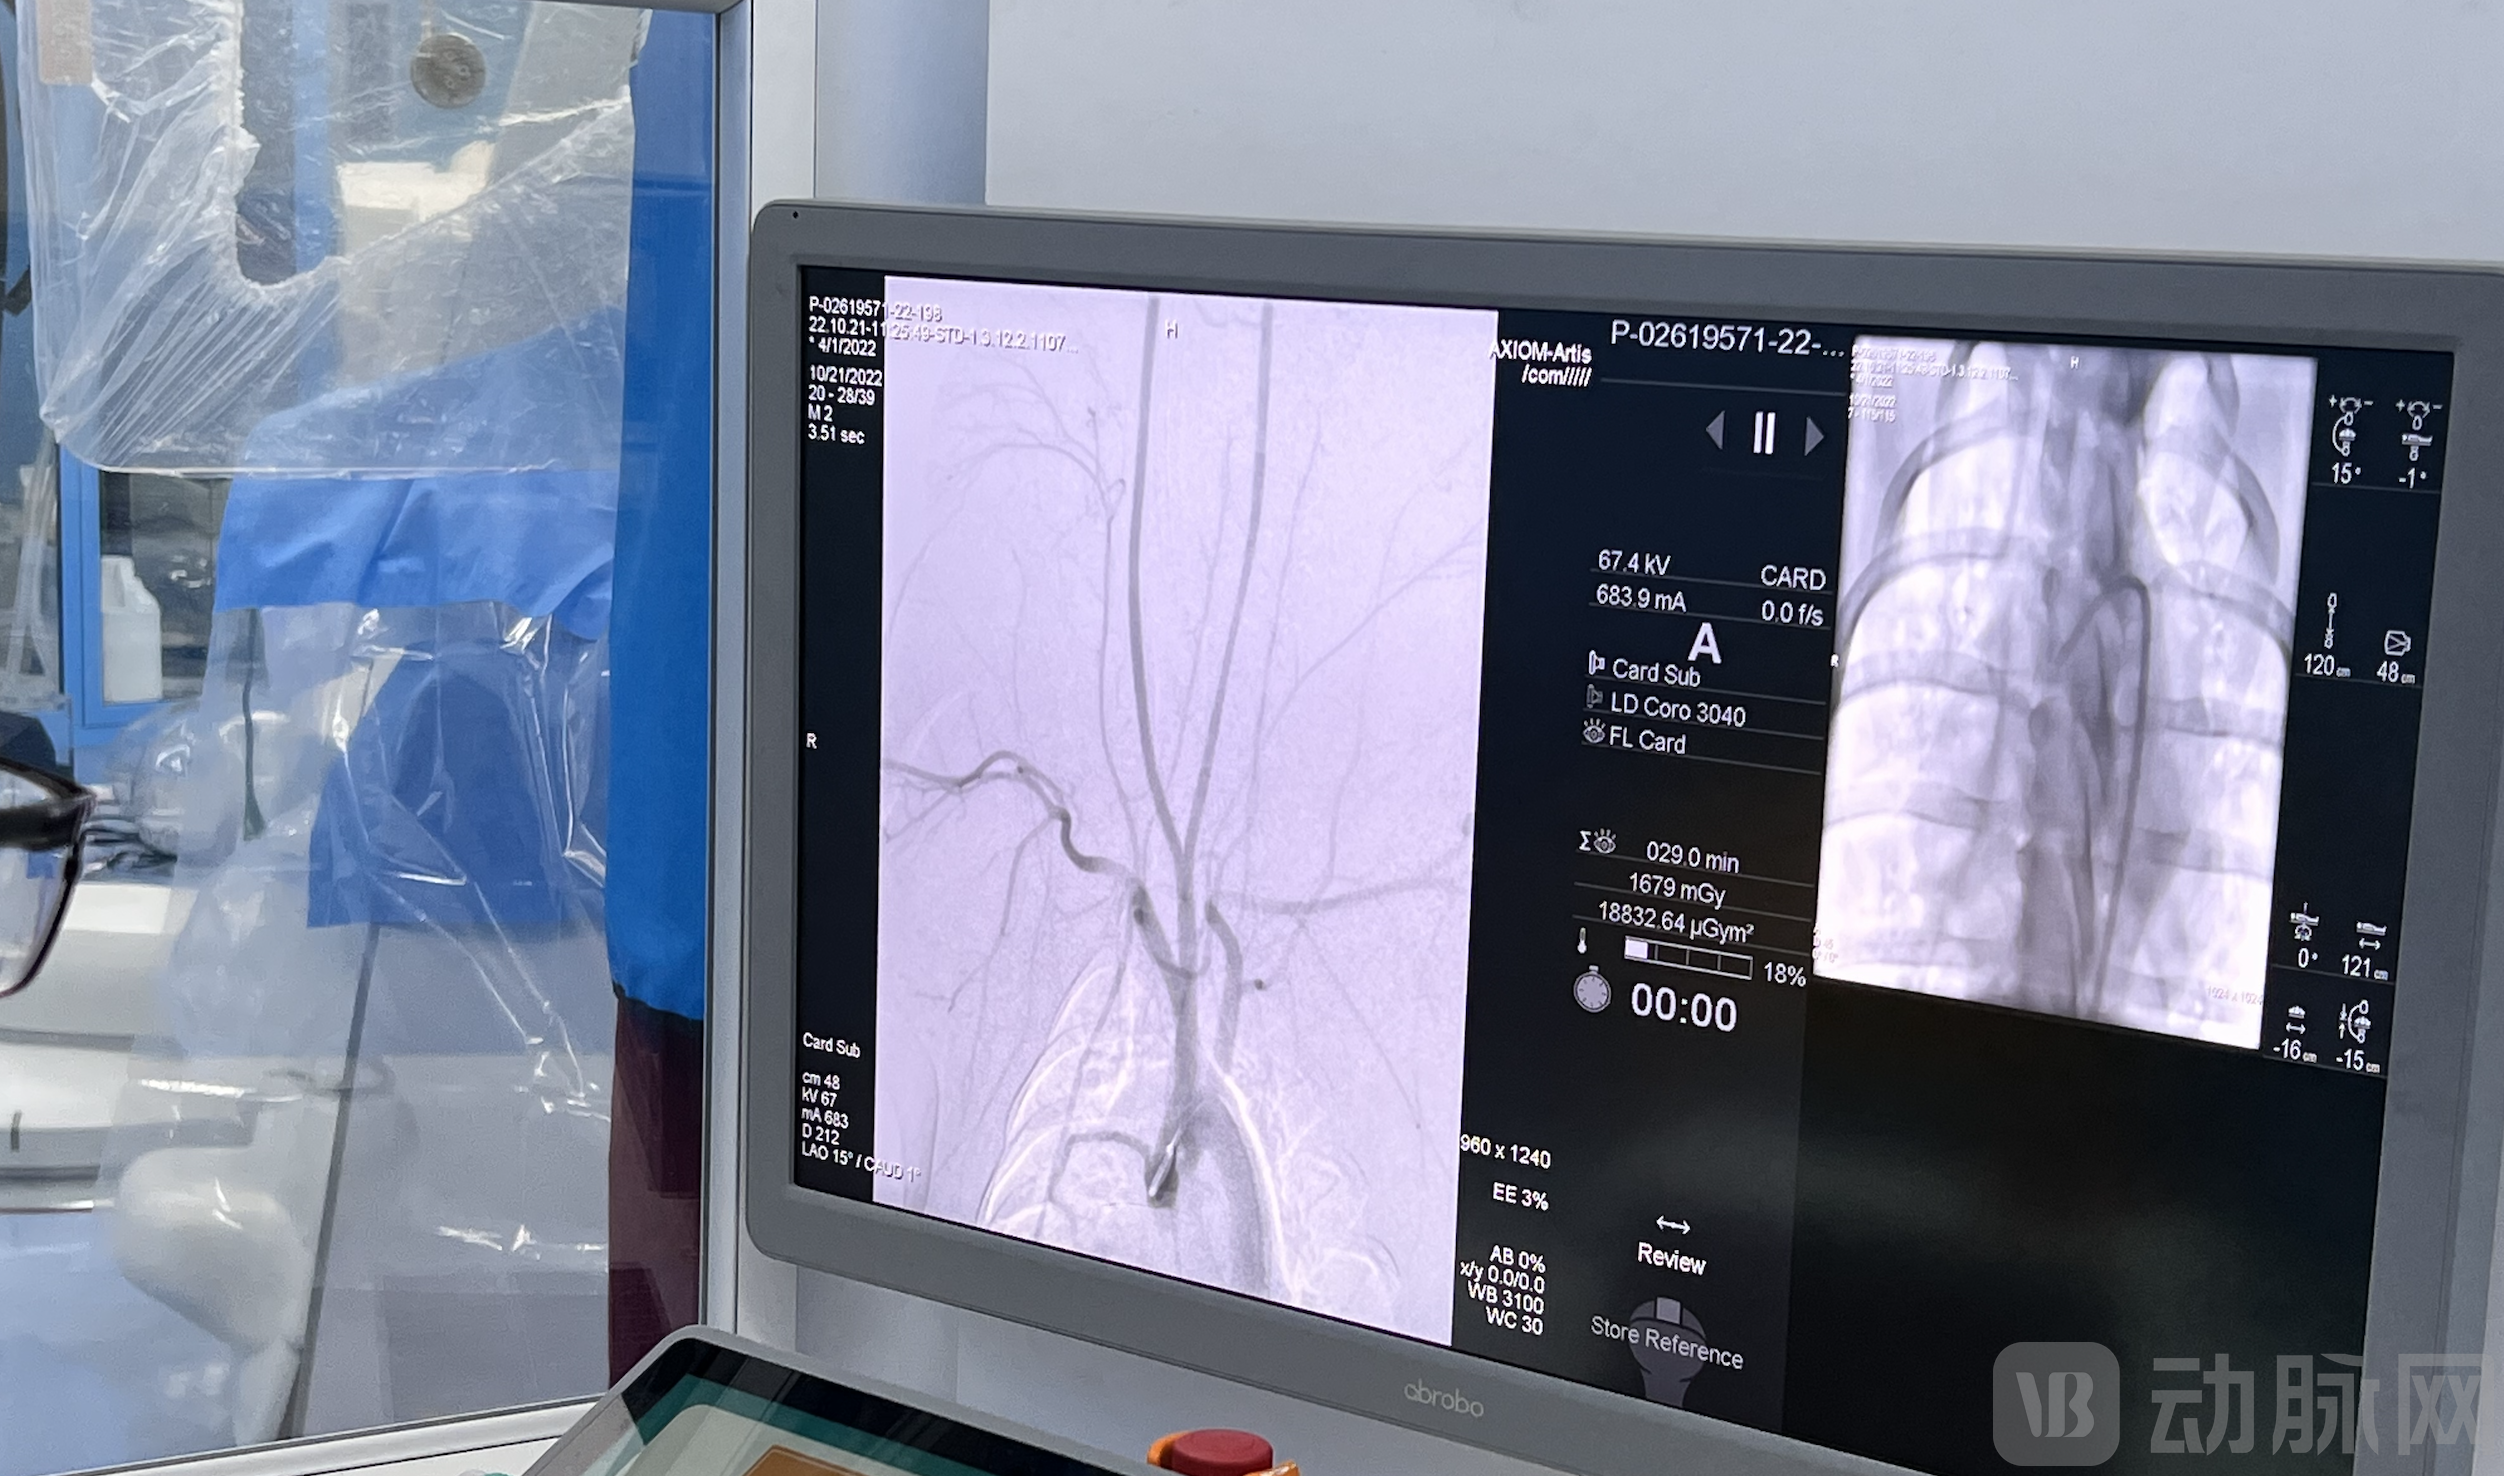

脑血管造影手术中

冠脉造影手术中